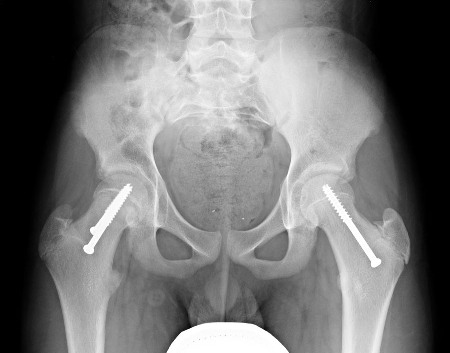

[Figure caption and citation for the preceding image starts]: Epifisiólise proximal do fêmur (EPF) instável no quadril direito fixo com 2 parafusos. Fixação profilática do quadril esquerdo com um único parafuso. Radiografia pós-operatória lateral com as pernas em posição de rãImagem cedida por John M. Flynn, MD [Citation ends].